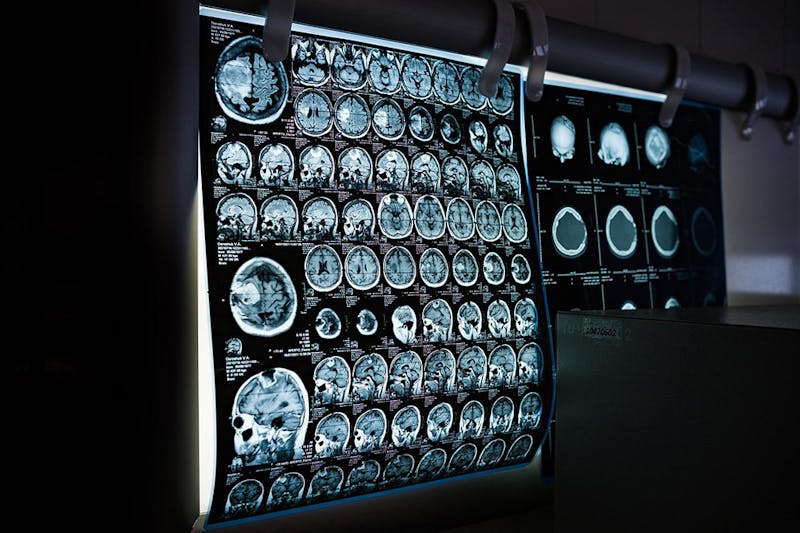

X-rays are one of the most commonly used diagnostic tools in the medical field. They allow doctors to see inside the body without having to perform surgery. However, doctors can misread X-rays much like any other diagnostic test or tool. In fact, despite the tremendous advancements in radiological science, data suggests that radiologists still misread X-rays 3-5% of the time.

The likelihood of errors also increases during the night shift hours of the day versus a lower chance during the day shift hours. Unfortunately, these mistakes can have devastating consequences for wrongfully diagnosed patients. You may be able to file a malpractice lawsuit if you or a loved one has been injured due to a radiologist’s mistake.